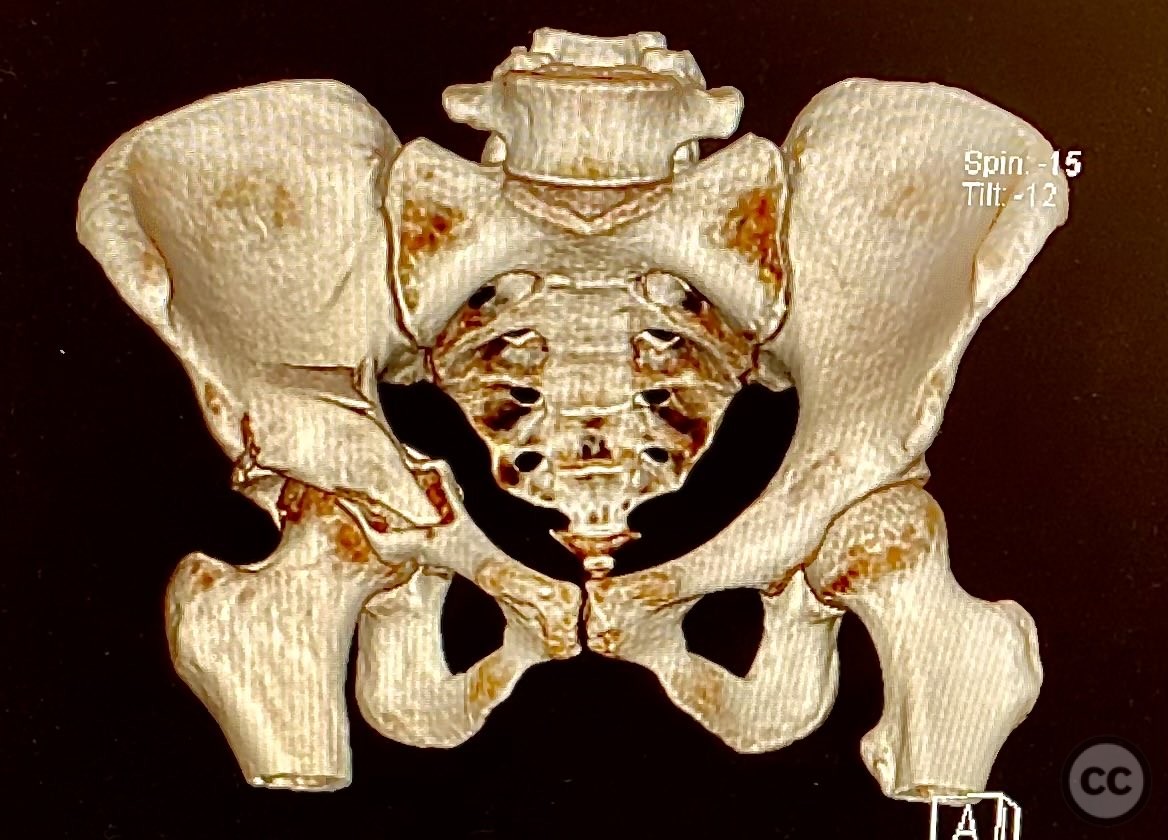

Clinical and radiological findings:  The patient sustained an acetabular fracture with a rare posterior medial dome impaction fragment, as demonstrated on AP pelvic radiographs obtained in skeletal traction. Surface renderings and axial CT images revealed multiple incomplete fracture lines, including a rhomboid-shaped cortical fragment adjacent and proximal to the anterior column/wall fragment. Coronal and sagittal reconstructions further delineated the impacted articular fragment and its relationship to the surrounding acetabular dome. The fracture pattern is classified as AO/OTA 62B3 (associated both-column fracture with dome impaction).